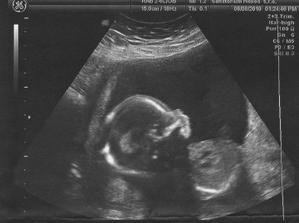

Dr. potvrdila těhotenství a poslala mě do porodnice na UTZ pro stanovení stáří - jsme 6+2 tt, miminko je tam, kde má být a bije mu srdíčko,

Průkazku jsme dostali 7.4. a dle UTZ odpovídáme 10+4 tt

Objednání na NT screening na 13.4. - odpovídáme 11+6 tt, máme všechny končetiny, srdíčko bije o 106 a výsledky testu jsou negativní !!